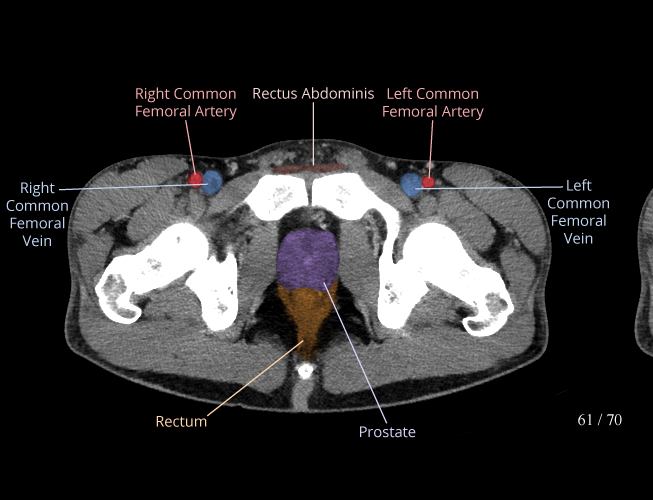

Pelvis

Covers pelvic MRI anatomy.